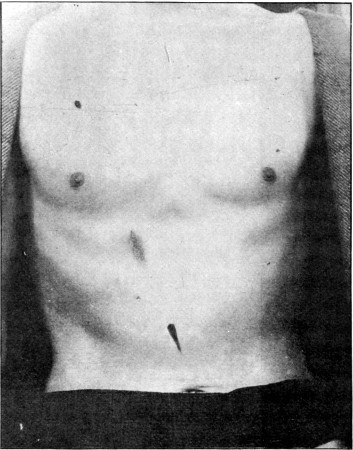

84. Subcutaneous Division of Abdominal Muscles409